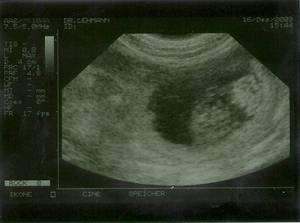

Und da so Allüren wie "mag Morgens kein Futter", "mir ist sooo schlecht", "hab Hunger auf ALLES" usw. auch schon da sind, können wir wohl als sicher annehmen: Angelina ist werdende Mutter! Erste Bilder von den Mini´s![]() ![]() Ich war bisher zwar noch nie, aber diesmal wegen der vielen Fragen war auch ich mit Angelina bei der Ultraschall-Untersuchung. Nachdem der erste Versuch am Dienstag gleich bei Eintritt in die Ordination des TA mit einem Knall, der den Ausfall des Gerätes signalisierte abgebrochen wurde, waren wir dann am Mittwoch, den 16. 12. andernorts erfolgreich.

Hier sind sie nun, die Bilder von Tag 29. Viel sieht man nicht, live war es schon spannender, mal hier ein Beinchen, mal hier eine Nase zu sehen - oder es sich zumindest einzubilden.

Auf den Bildern sieht man ja sowieso immer nur Einzelne oder maximal zwei, aber soweit Arzt und ich das sehen konnten sind es mindestens sechs Mini´s, die sich da auf die grosse weite Welt vorbereiten.